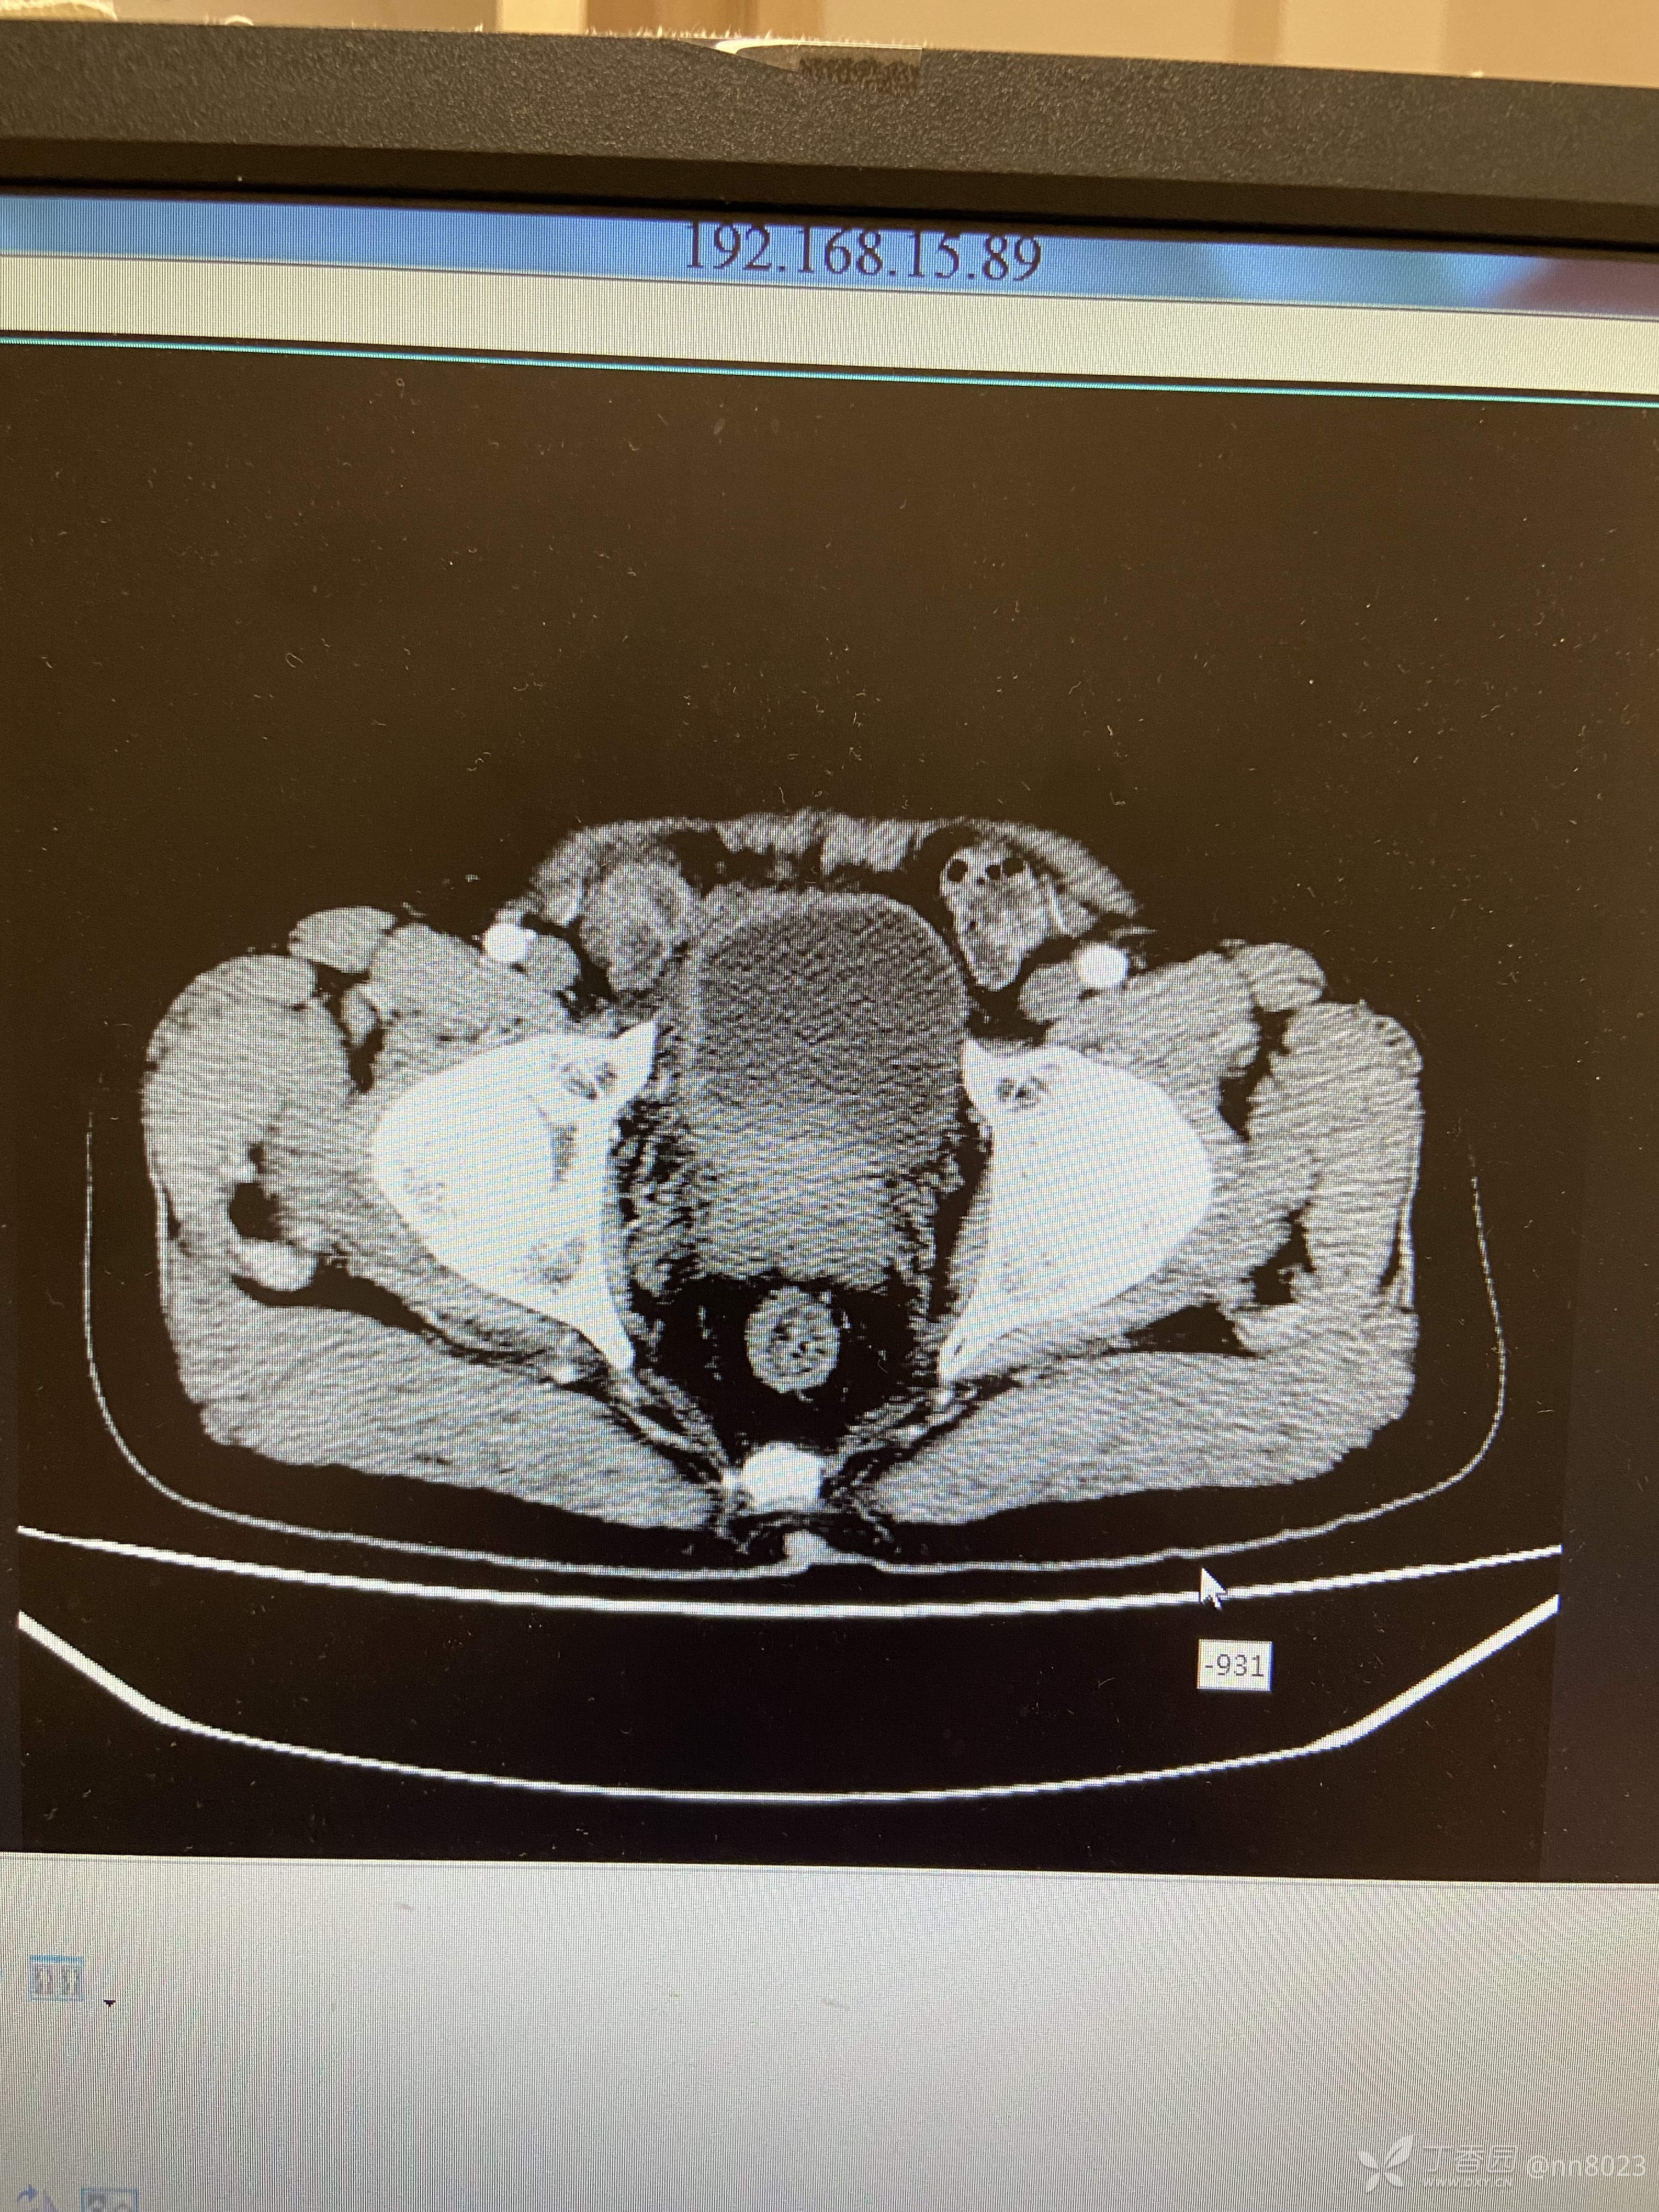

xiaospring +3 丁当66岁男性患者,因尿频尿痛于当地医院检查,彩超提示膀胱占位,完善增强CT

后面又做了经输尿管镜检查(视频见下一个帖子),输尿管末端狭窄,其上方输尿管扩张明显,未见明显占位性病变,膀胱内组织已取活检,待病理。